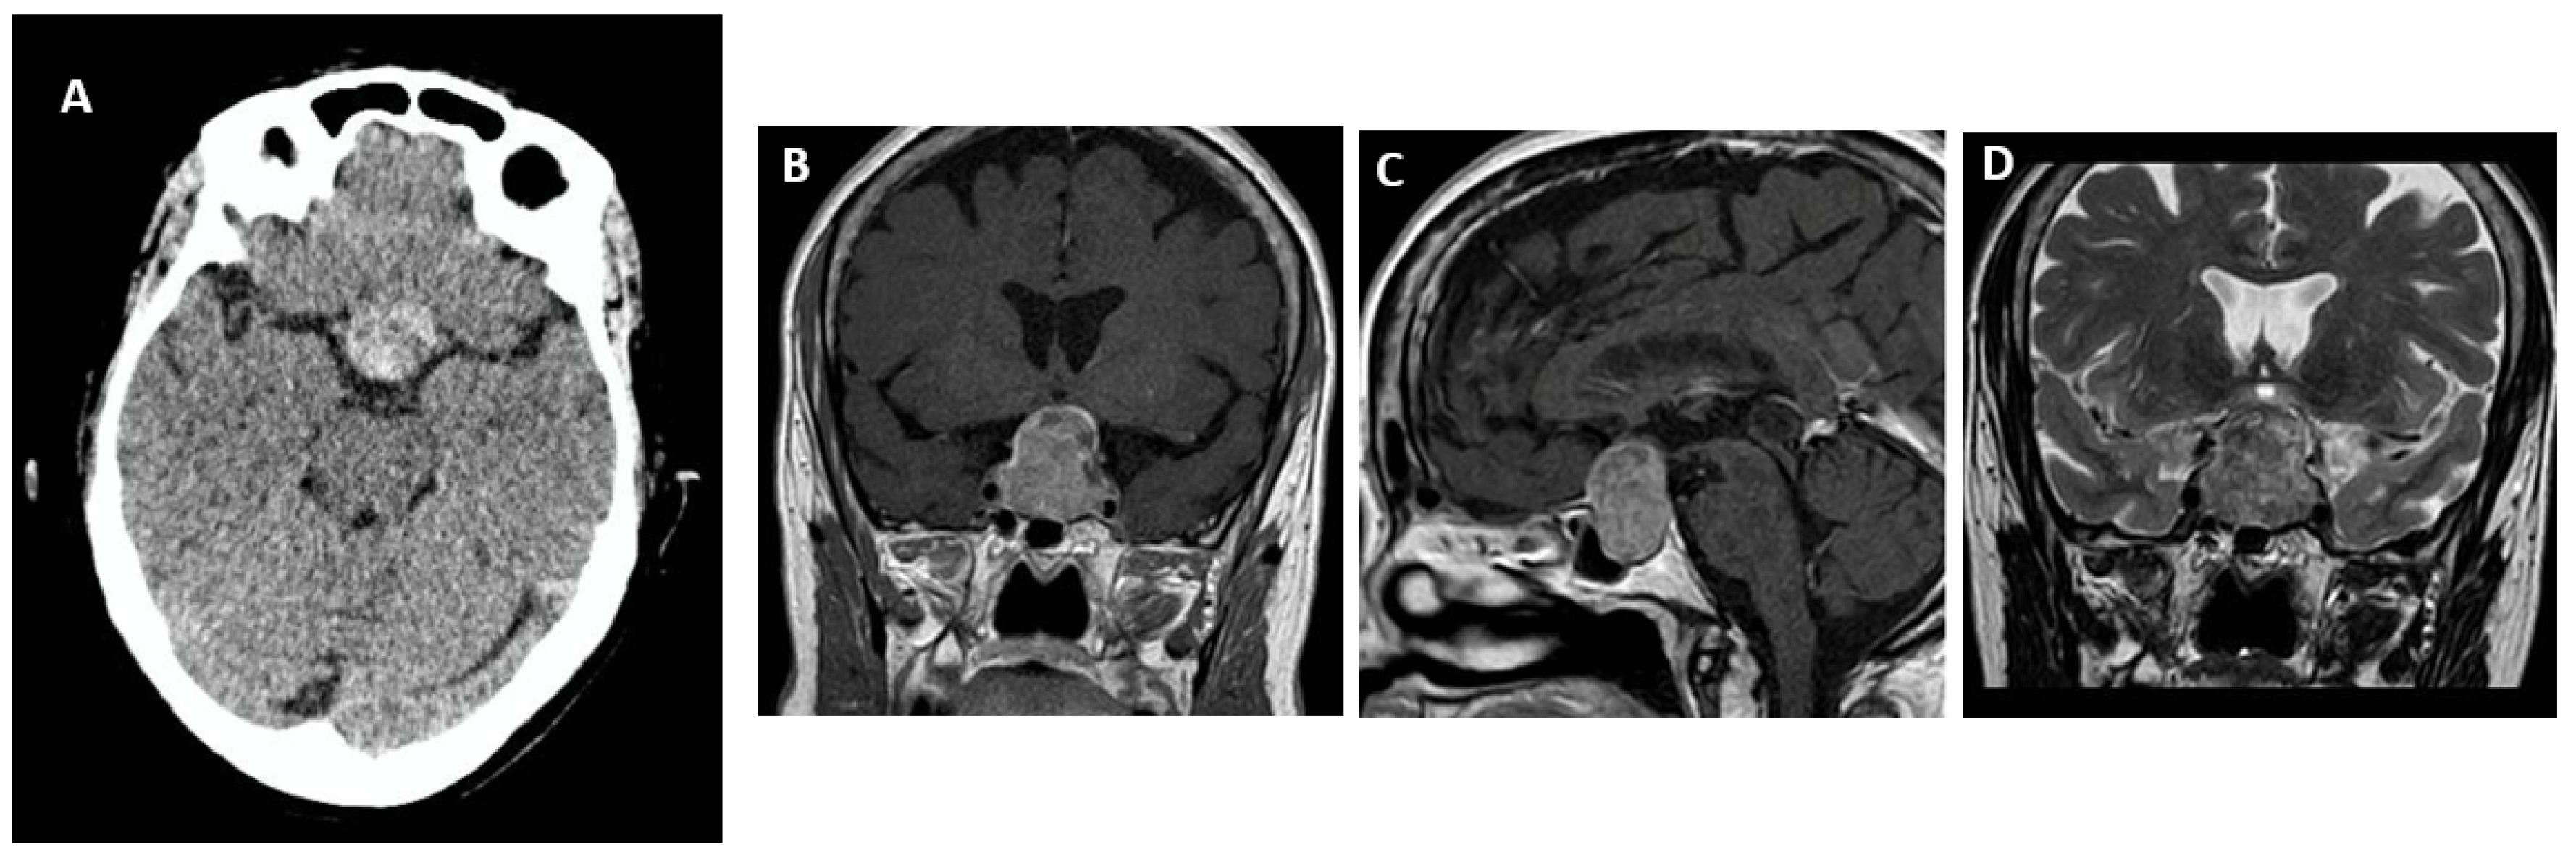

- Boellis, A.; di Napoli, A.; Romano, A.; Bozzao, A. Pituitary Apoplexy: An Update on Clinical and Imaging Features. Insights Imaging 2014, 5, 753–762. [Google Scholar] [CrossRef]